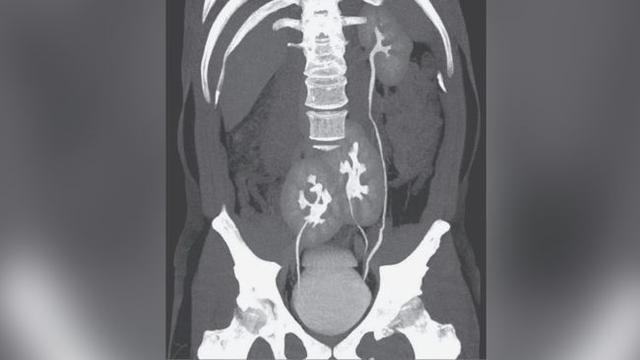

Căn bệnh khiến 10 người Việt có 1 người đi tiểu không kiểm soát

Theo thống kê nước ta có khoảng 10 triệu người có triệu chứng của bàng quang tăng hoạt, một bệnh lý khiến bệnh nhân tiểu gấp, tiểu nhiều lần, tiểu không kiểm soát, tiểu đêm.